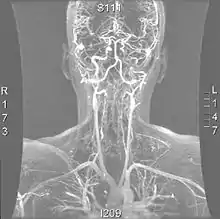

![]() | |

| Arteries of the neck, with arrows indicating the right vertebral artery | |